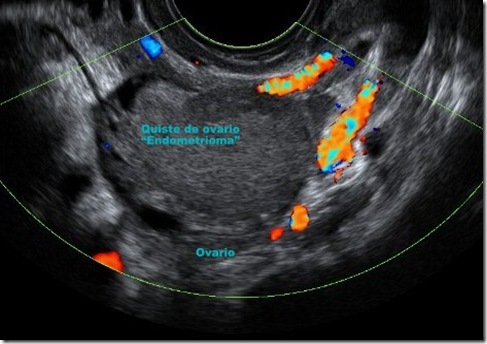

El ultrasonido endovaginal constituye una prueba diagnóstica extraordinaria. Se puede detectar la imagen del quiste endometriósico dentro del ovario con ciertas características que apoyan su diagnóstico, además de que el estudio vascular realizado durante el mismo, ayuda también para ello.

En la imagen se puede apreciar la silueta ovárica y en su interior se delimita el quiste en su interior llamado “endometrioma”. El tratamiento del endometrioma es quirúrgico.